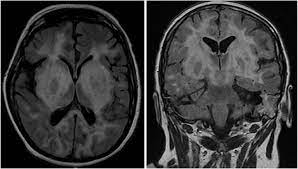

Lesions similar to cytotoxic edema, and lesions similar to vasogenic edema. Seizure, altered sensorium, fever frontal and temporal lobes, rarely extratemporal t2 hyperintensity, restricted diffusion, sometimes. Herpes encephalitis is the most common sporadic encephalitis in the united states and other industrialized countries .occurring as either a primary infection with herpes simplex virus or as a reactivation of latent virus, herpes encephalitis causes significant morbidity and mortality .early intervention with acyclovir significantly improves outcome; The clinical syndrome is often characterized by the rapid onset of fever, headache, seizures, focal neurologic signs, and impaired consciousness 1 . Having said that, mri with contrast is considered the most sensitive imaging modality, and findings are present in over half of individuals 8. The patients with the former type of lesions had fulminating disease, and were in severe clinical condition. Herpes simplex encephalitis occurs as 2 distinct entities: 4 it was found that, rather surprisingly, varicella zoster virus (vzv), the cause of chickenpox and herpes zoster, was the most frequently detected virus at 29%, with hsv and enteroviruses accounting for 11% of cases. Two subtypes are recognized which differ in demographics, virus, and pattern of involvement. (1)department of radiology, ankara numune education and research hospital, ankara, turkey. Neonatal herpes simplex encephalitis is caused by vertical transmission of infection during passage from birth canal with diffuse cerebral involvement within the first month after birth; As the older term limbic encephalitis implies, the most common location of involvement is the mesial temporal lobes and limbic systems, typically manifested by cortical thickening and increased t2/flair. In patients with herpes encephalitis, two distinct types of diffusion imaging findings (on b =1000 s/mm 2 images, and adc maps) were noted:

For viral infection of the meninges, please refer to the general article on viral meningitis, and, for a broad view on the curriculum of infections of the central nervous system, refer to cns. Two subtypes are recognized which differ in demographics, virus, and pattern of involvement. A recent study in finland also used pcr to detect various viruses in the csf of over 3000 patients who had infections of the cns including encephalitis, meningitis, and myelitis. The patients with the former type of lesions had fulminating disease, and were in severe clinical condition. Despite advances in antiviral therapy over the past 2 decades, herpes simplex encephalitis (hse) remains a serious illness with significant risks of morbidity and death. Normal mr imaging findings (type 1, 53% of patients), isolated hippocampal involvement (type 2, 13%), other brain lesions without hippocampal involvement (type 3, 13%), and other brain lesions with hippocampal involvement (type 4, 21%). Lesions similar to cytotoxic edema, and lesions similar to vasogenic edema. As the older term limbic encephalitis implies, the most common location of involvement is the mesial temporal lobes and limbic systems, typically manifested by cortical thickening and increased t2/flair.

We present mri findings of two cases of herpes simplex encephalitis (hse) confirmed by pcr analysis, focusing on the serial changes after acyclovir therapy: 4 it was found that, rather surprisingly, varicella zoster virus (vzv), the cause of chickenpox and herpes zoster, was the most frequently detected virus at 29%, with hsv and enteroviruses accounting for 11% of cases. mri findings of herpes simplex encephalitis. For viral infection of the meninges, please refer to the general article on viral meningitis, and, for a broad view on the curriculum of infections of the central nervous system, refer to cns. The patients with the former type of lesions had fulminating disease, and were in severe clinical condition. The kappa value for interobserver agreement on rating the scans as normal or abnormal was good (0.65) for ct and moderate (0.59) for mri. Noguchi t, yoshiura t, hiwatashi a, et al. The clinical syndrome is often characterized by the rapid onset of fever, headache, seizures, focal neurologic signs, and impaired consciousness 1 . The patients with the former type of lesions had fulminating disease, and were in severe clinical condition. Specific diagnosis often requires pcr. As the older term limbic encephalitis implies, the most common location of involvement is the mesial temporal lobes and limbic systems, typically manifested by cortical thickening and increased t2/flair. In patients with herpes encephalitis, two distinct types of diffusion imaging findings (on b =1000 s/mm 2 images, and adc maps) were noted: A recent study in finland also used pcr to detect various viruses in the csf of over 3000 patients who had infections of the cns including encephalitis, meningitis, and myelitis.